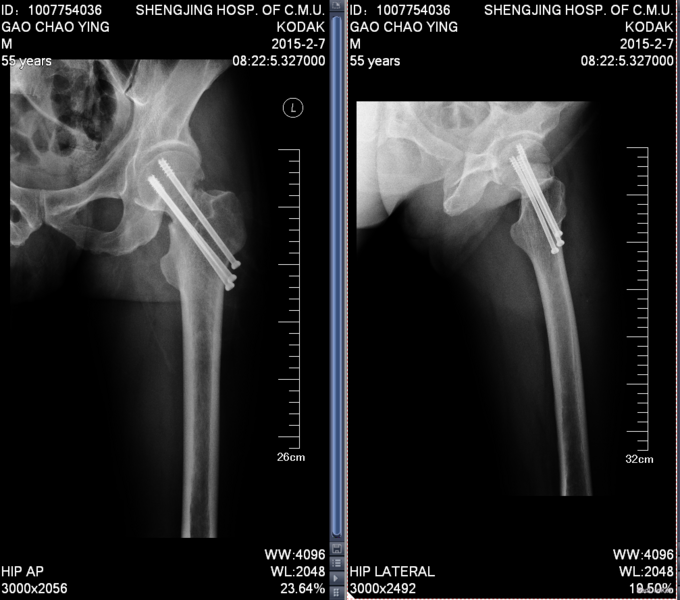

患者入院后完善相关检查,查无明显手术禁忌症后行左股骨颈骨折闭合复位空心钉内固定术。患者术后卧床休息,给予接骨等对症治疗。